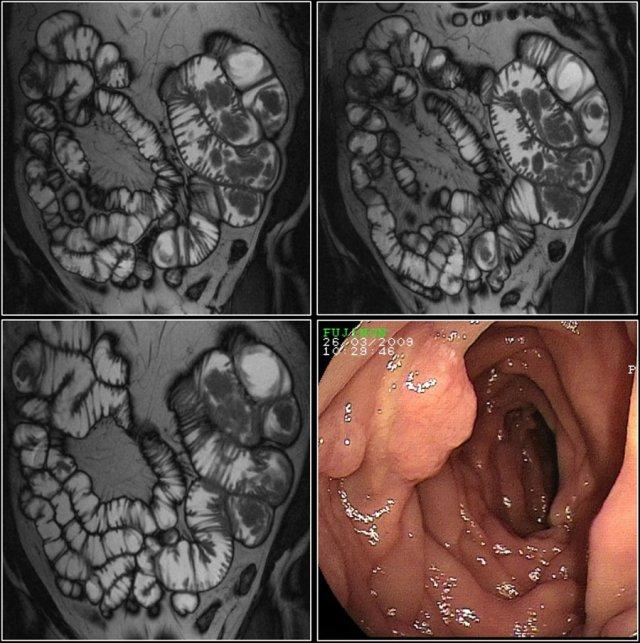

Đây là bệnh nhân mắc hội chứng Peutz-Jeghers với nhiều polyp ruột non, chủ yếu ở hỗng tràng.

Hội chứng đa polyp

Các hội chứng đa polyp đường ruột có thể được phân thành các nhóm lớn: đa polyp tuyến có tính gia đình (như hội chứng Gardner), hội chứng đa polyp hamartoma (như hội chứng Peutz-Jeghers) và các hội chứng đa polyp hiếm gặp khác.

Bệnh nhân mắc các hội chứng này thường có nhiều polyp ruột non.

Các polyp lớn hơn có thể trở nên ác tính và có thể bắt chước các u tân sinh ruột non nguyên phát.

Đây là bệnh nhân mắc hội chứng Peutz-Jeghers với nhiều polyp ở hỗng tràng.

Polyp lớn nhất ở bệnh nhân này đã được cắt bỏ qua nội soi.

U máu được xác nhận bằng giải phẫu bệnh: chuỗi xung T1 FS sau tiêm thuốc tương phản từ mặt phẳng coronal và chuỗi xung T2W coronal cho thấy khối trong lòng hỗng tràng bờ rõ có ngấm thuốc.

U máu (Hemangioma)

Hầu hết u máu đường ruột có vị trí ở hỗng tràng.

Chúng có thể không cuống hoặc có cuống, và thường ngấm thuốc dạng nốt trong thì động mạch và ngấm thuốc đồng nhất trong thì muộn.